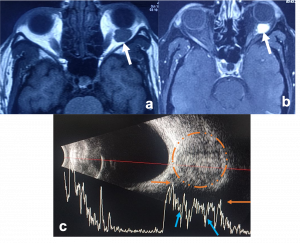

Cavernous Malformation. a) Axial T1WI MRI shows a left intraconal ovoid, well encapsulated soft tissue mass that indents the posterior aspect of the eye globe associated with mild proptosis. b)Post contrast axial T1WI with fat suppression demonstrates progressive heterogeneous bright enhancement (white arrow) of the lesion c) USG orbit (B/A) showing a well encapsulated mass on B scan (orange circle) with corresponding internal acoustic reflections on A scan showing characteristic dancing spikes demonstrating rise and fall of waves as it traverses through multiple blood-filled channels within the tumor (blue arrows) |